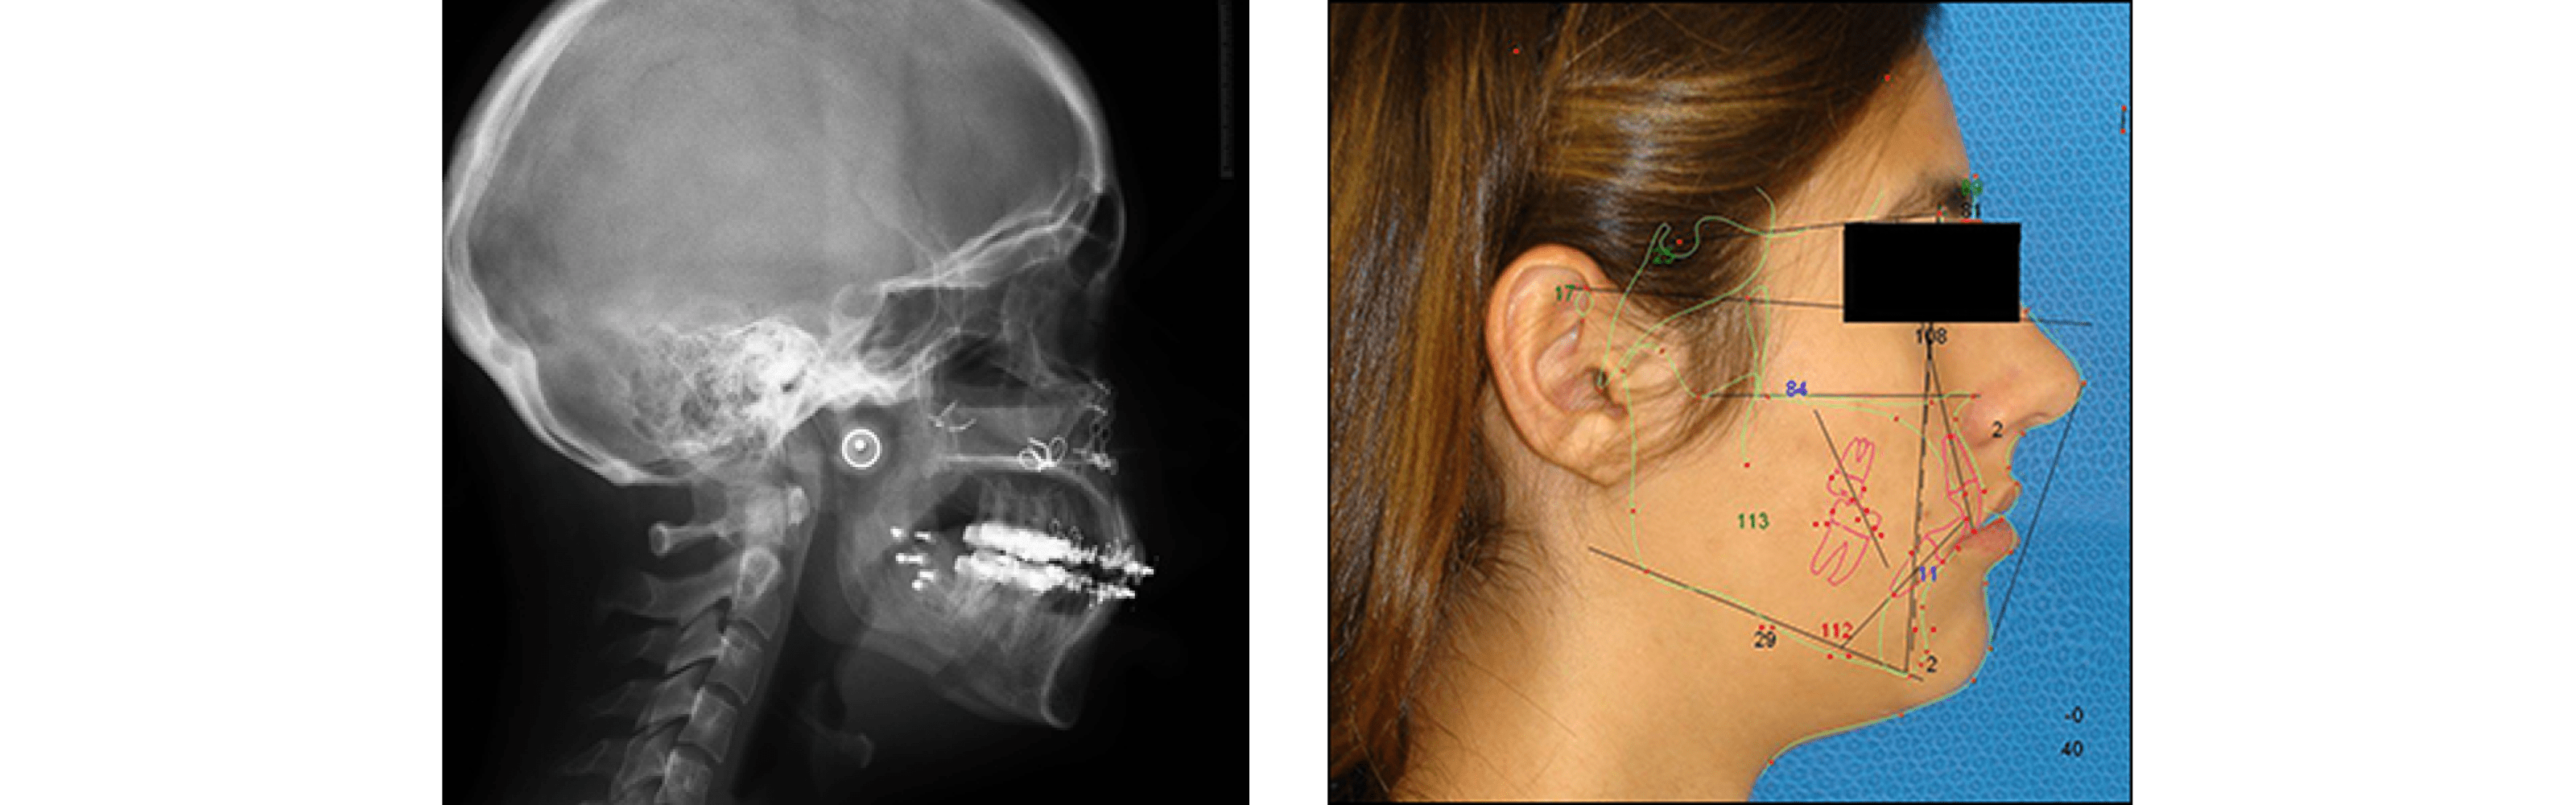

The diagnosis of sleep apnea is made based in the signs and symptoms and other studies. With cephalometric (skull x-ray) analysis, the oral and maxillofacial surgeon can ascertain the level of obstruction. Sometimes a naso-pharyngeal exam is done with a flexible fiber-optic camera. To confirm the amount of cardiovascular compromise and decreased oxygenation levels, a sleep study may be recommended to monitor individuals overnight.

Orthognathic surgery is needed when jaws do not meet correctly and/or teeth do not seem to fit with jaws. Teeth are straightened with orthodontics and corrective jaw surgery repositions misaligned jaws. This not only improves facial appearance, but also ensures that teeth meet correctly and function properly. The causes of a misaligned jaw go from birth defects, trauma or abnormal growth.

The first step in repositioning a misaligned jaw is a thorough examination through x-rays, photos and models of your jaws and teeth. This type of procedure typically has to be coordinated together between your oral & maxillofacial surgeon and your orthodontist. The latest will then align your teeth with braces and the surgeon will operate in the maxilla, mandible or both jaws. The procedure is performed in the hospital under general anesthesia and the patient can be discharge the same day or the day after the surgery. Once surgery is completed, your teeth and jaws will have been moved into a new, more attractive position that will provide you with better jaw functionality and excellent facial appearance. The results of orthognathic surgery are permanent.